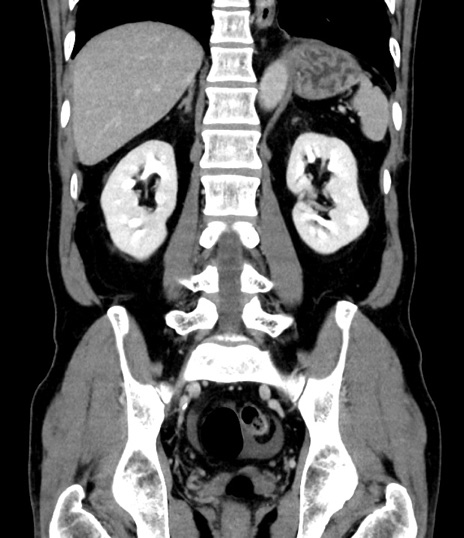

症例8(冠状断像)

【症例】 60歳代男性

【主訴】 黒色吐物

【現病歴】 4日前から嘔気自覚、2日前の朝食後にも嘔気あり、自分で手で嘔吐反射起こし嘔吐したところ血が混ざっていたため受診。

【既往歴】 5年前汎発性腹膜炎を伴う急性虫垂炎で手術、高血圧、前立腺肥大症、高脂血症

【身体所見】 腹部正中に手術癩痕あり 腹部平坦・軟圧痛なし膨満感あり

【データ】WBC 8400、CRP 4.54